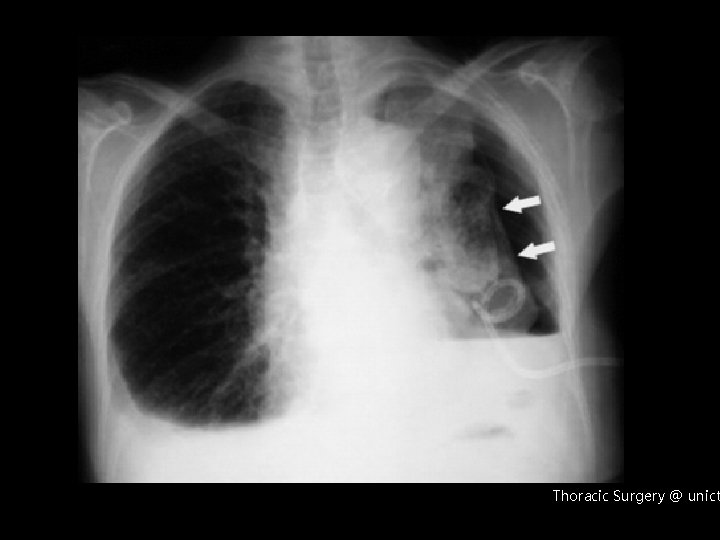

Scuola di Specializzazione in chirurgia toracica (Prof. M. Migliore) Scuola di Specializzazione in malattie apparato respiratorio (Prof. De Maria) Scuola di specializzazione in radiologia (Prof. ) Versamento pleurico maligno: Indicazioni al trattamento chirurgico Prof. Marcello Migliore Thoracic Surgery @ unict

Malignant pleural effusions are an important complication for patients with intrathoracic and extrathoracic malignancies. Median survival after diagnosis of an MPE is 4 months. Thoracic Surgery @ unict